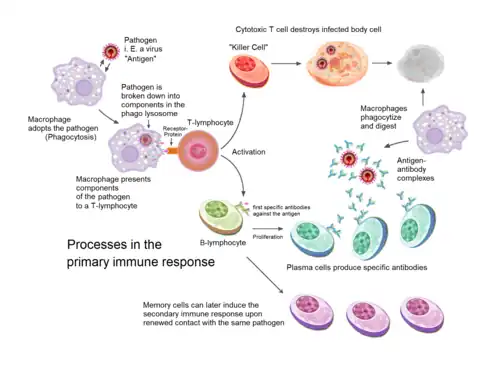

Immune system

The immune system consists of the white blood cells, the thymus, lymph nodes and lymph channels, which are also part of the lymphatic system. The immune system provides a mechanism for the body to distinguish its own cells and tissues from outside cells and substances and to neutralize or destroy the latter by using specialized proteins such as antibodies, cytokines, and toll-like receptors, among many others.[31]